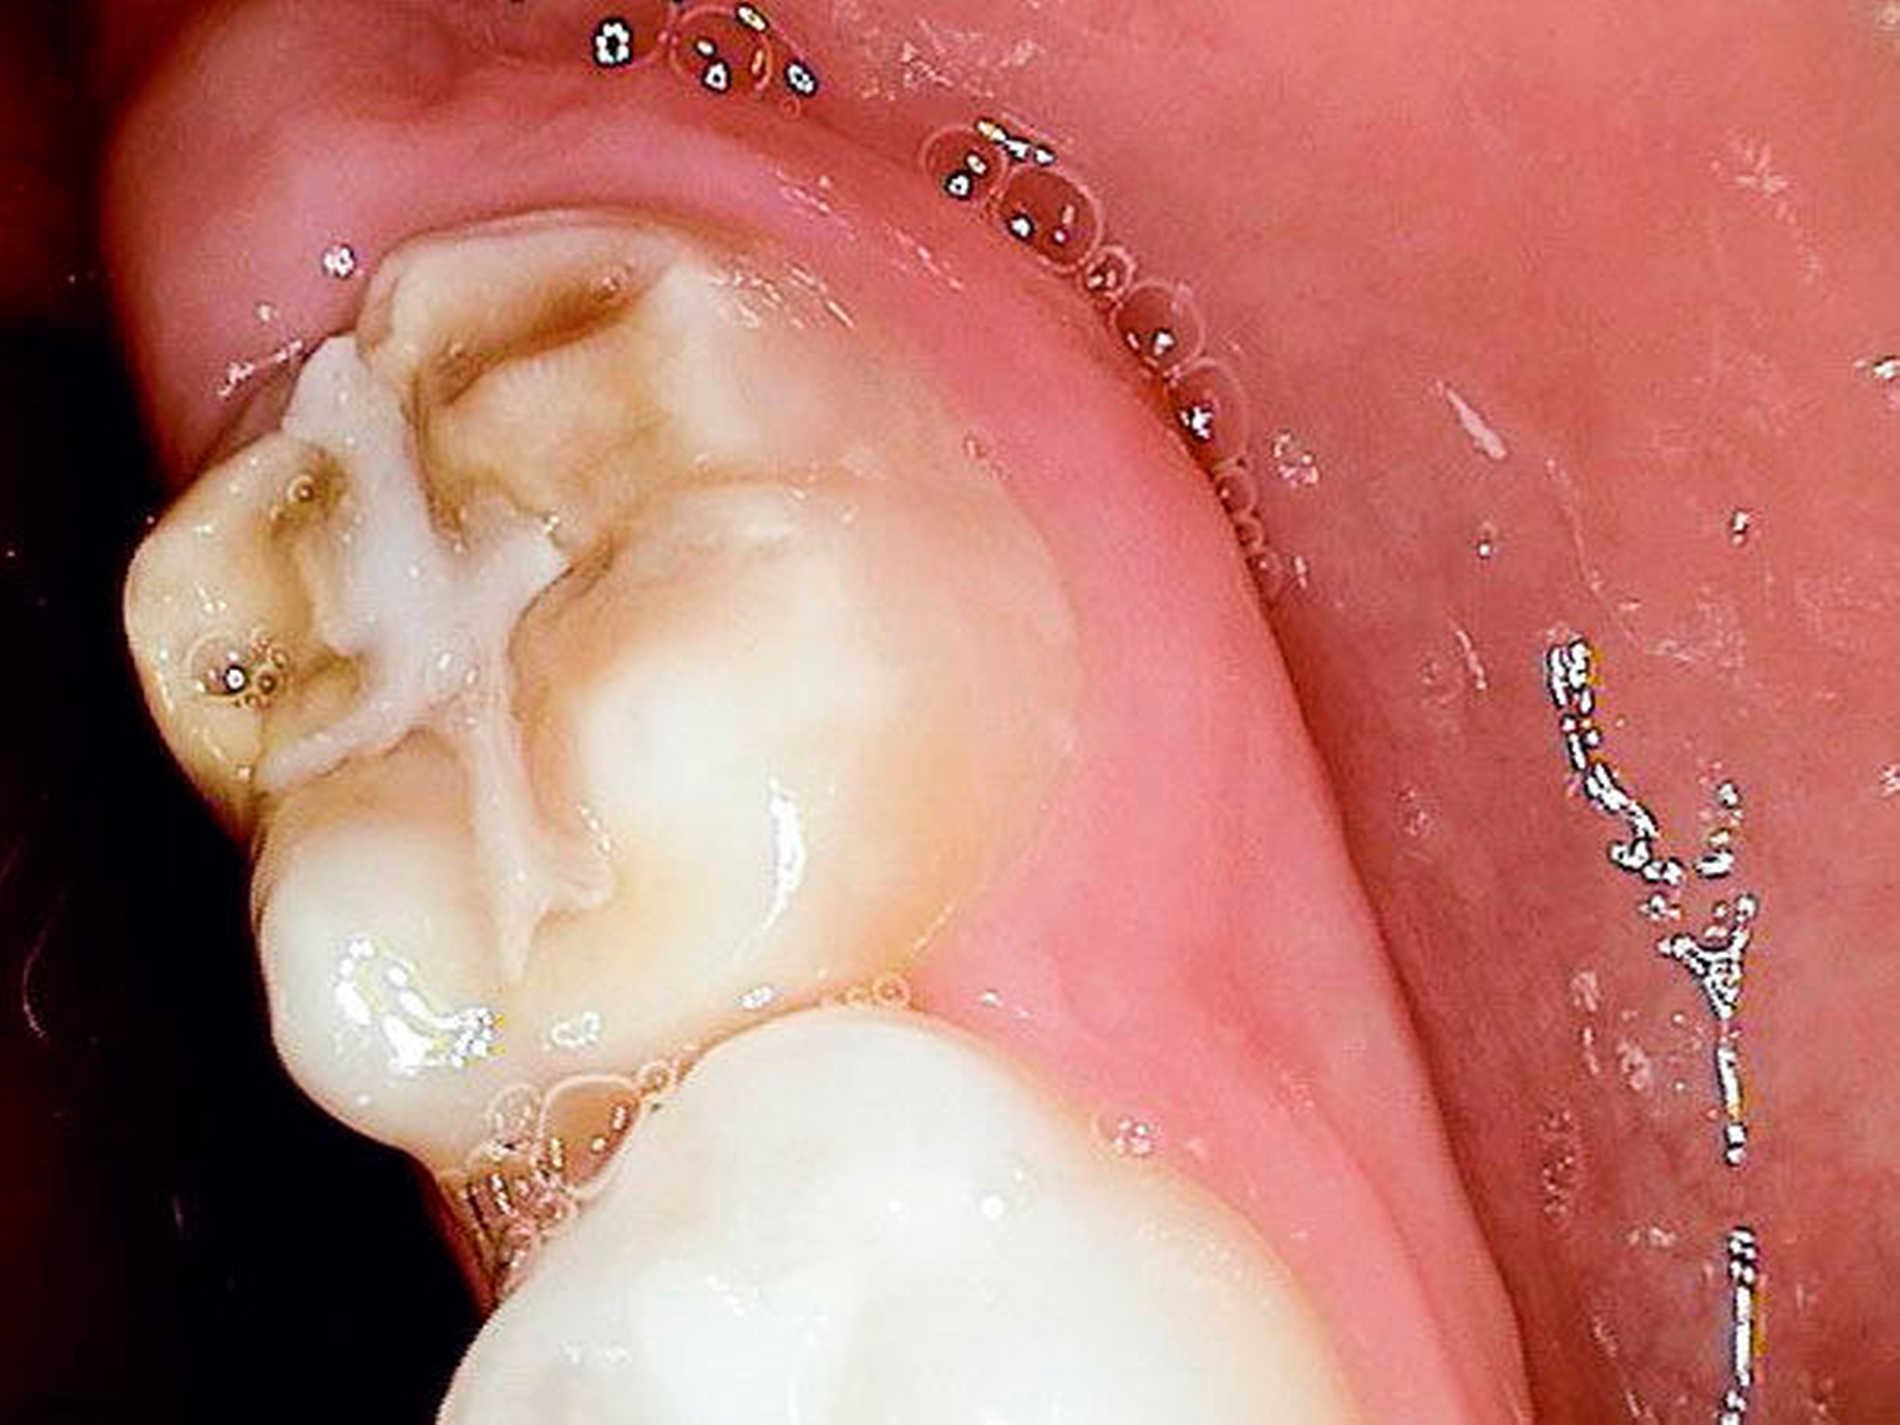

Zweiter Befund nach drei Jahren:Im April 2011 stellte sich der Patient erneut im ZFZ vor. Mittlerweile war der Patient sieben Jahre alt und im beginnenden Wechselgebiss zeigten sich Schmelzhypoplasien der Sechsjahresmolaren (Abbildungen 3 bis 5). Da die Zähne starke Empfindlichkeiten und zunehmende Substanzverluste trotz versuchter Fissurenversiegelungen aufwiesen, hat der Hauszahnarzt mit den Eltern entschieden, diese weiter versorgen zu lassen. Somit wurde der Patient wieder ans ZFZ überwiesen zur erneuten ITN-Behandlung.

Befund:Abgesehen von einer insgesamt verzögerten körperlichen und dentalen Entwicklung aufgrund der Vorerkrankung, zeigte sich der extraorale Befund unauffällig, der intraorale Befund zeigte ein Wechselgebiss. An allen ersten Milchmolaren konnte Approximalkaries festgestellt werden. Alle Sechsjahrmolaren sowie die Schneidezähne im Ober- und im Unterkiefer waren, unterschiedlich ausgeprägt, von MIH betroffen. Das Zähneputzen und Essen wurde zunehmend zur Belastung aufgrund der Schmerzempfindlichkeit. Außerdem wurde Substanzverlust an Zahn 46 bemerkt (Abbildungen 9 und 10).